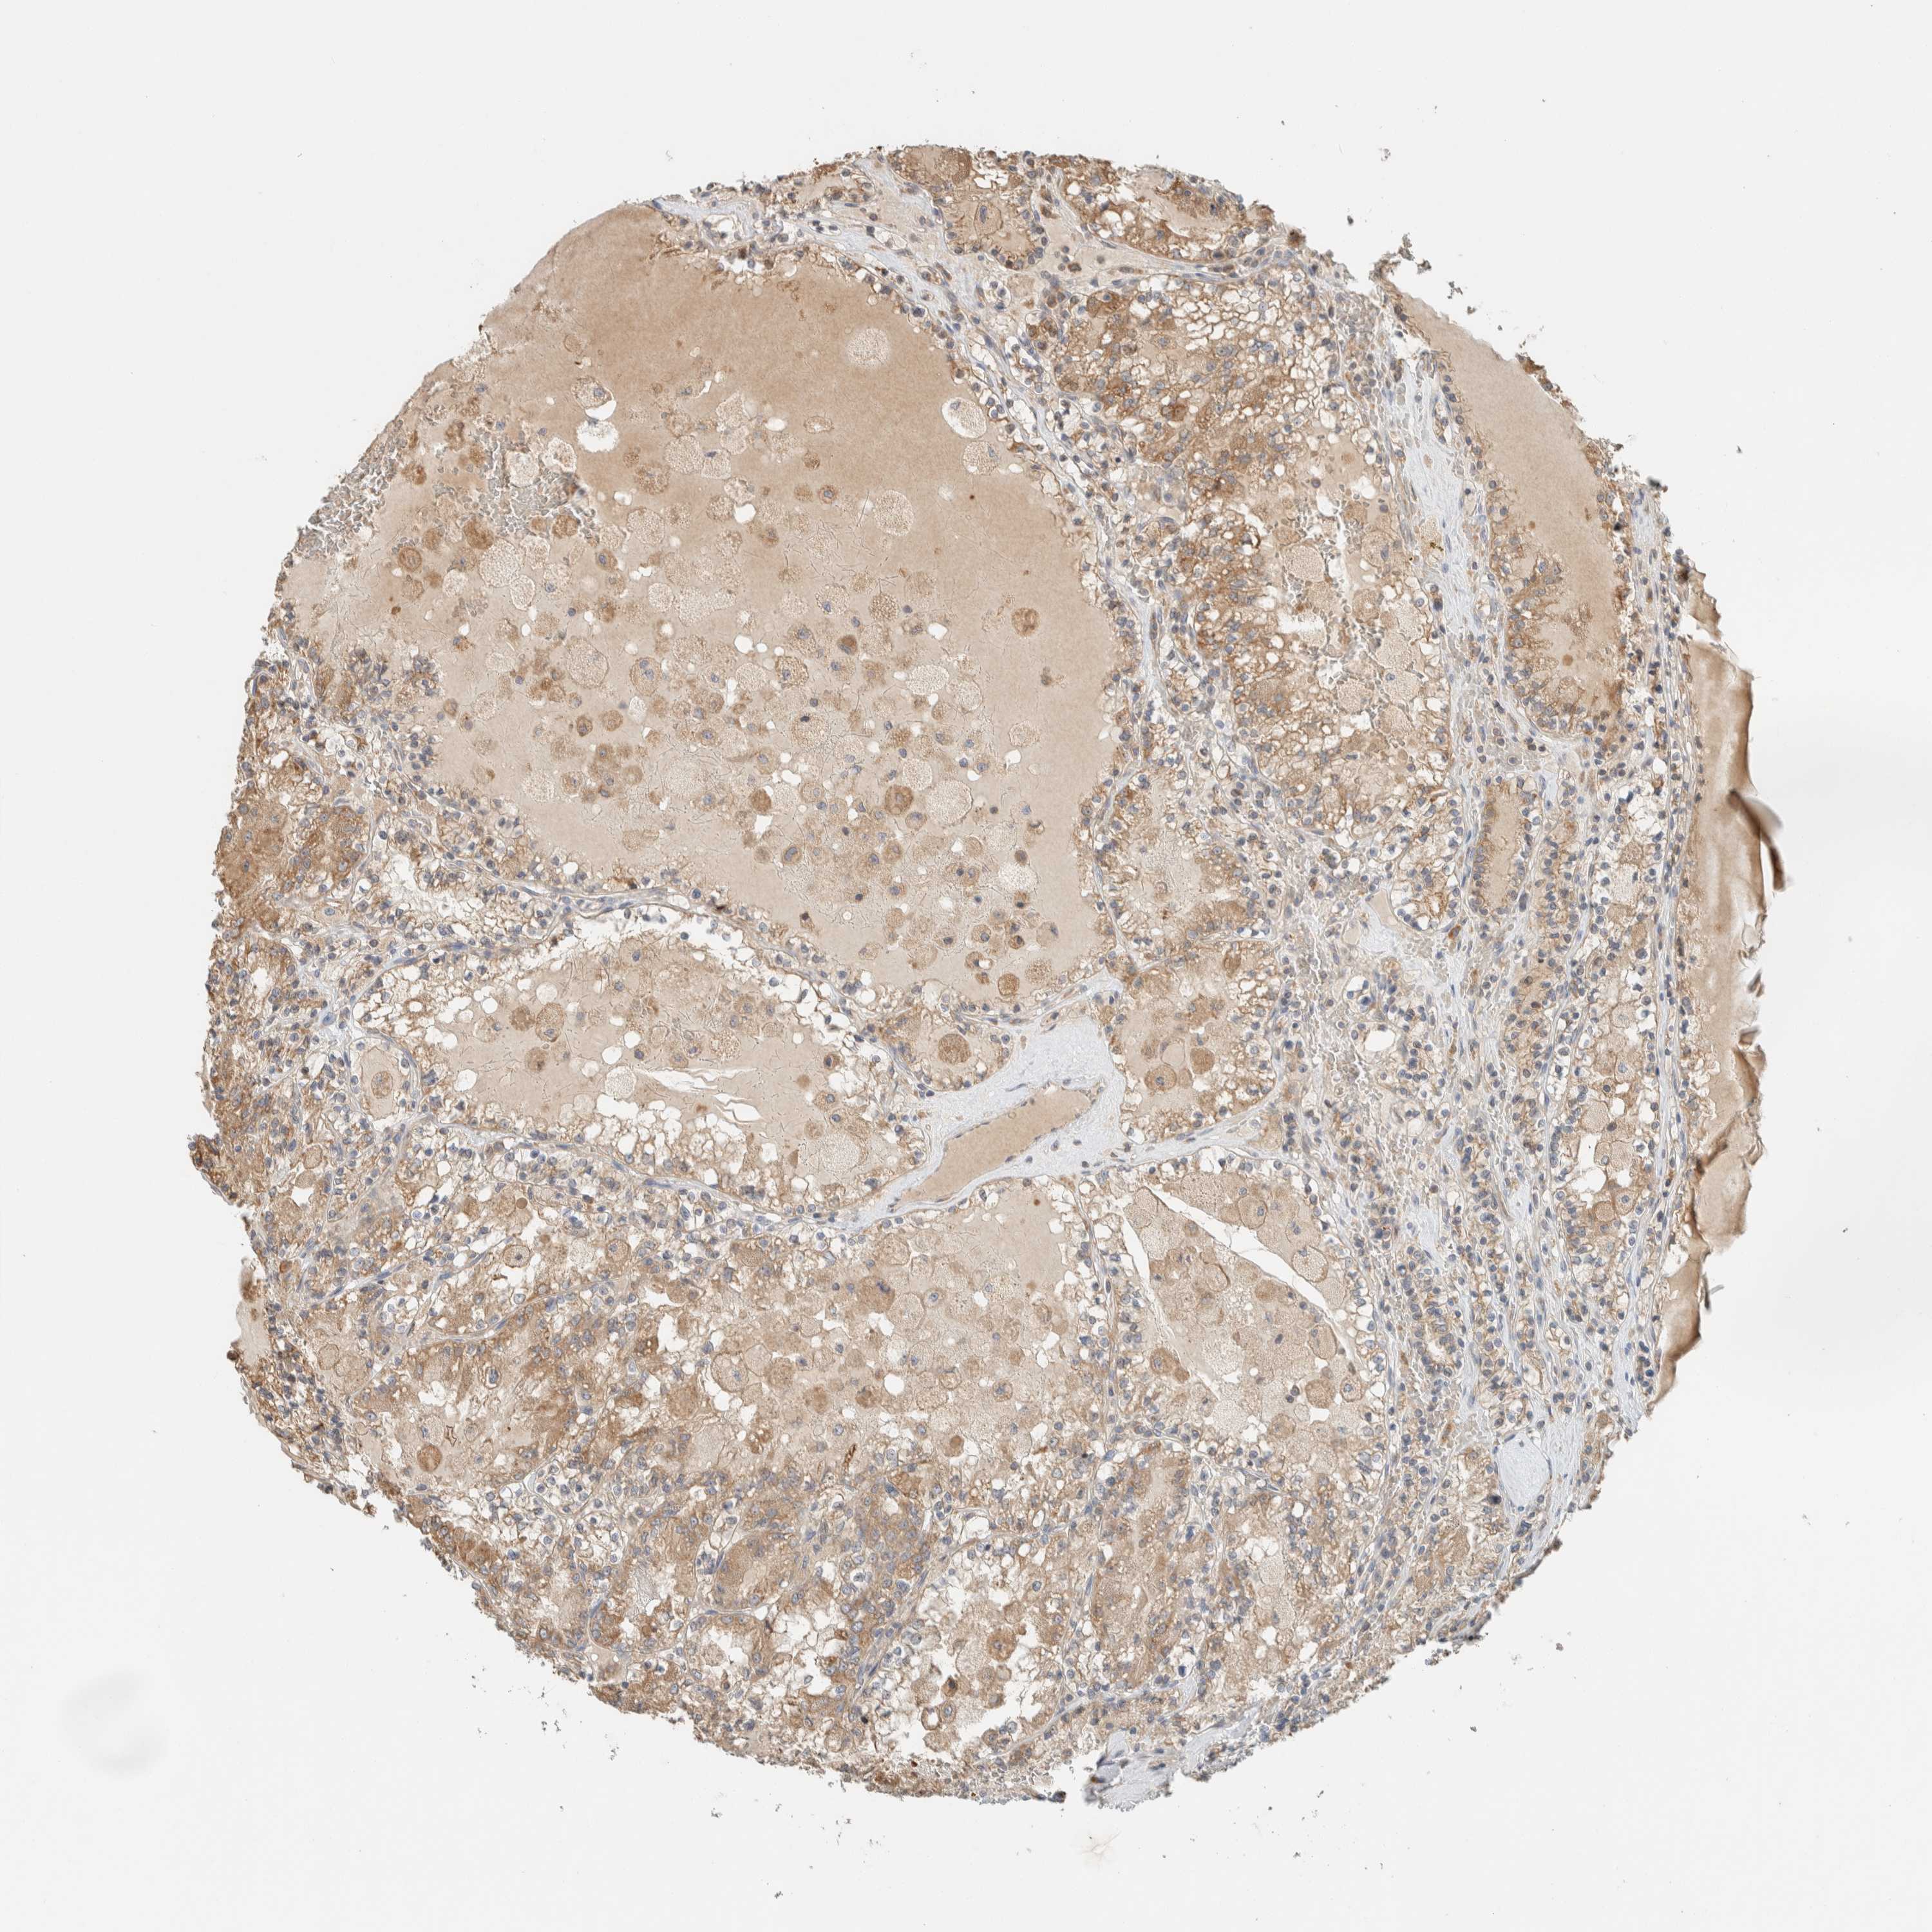

KIDNEY RENAL PAPILLARY CELL CARCINOMA (TCGA) - Interactive survival scatter ploti

The Survival Scatter plot shows the clinical status (i.e. dead or alive) for all individuals in the patient cohort, based on the same data that underlies the corresponding Kaplan-Meier plots. Patients that are alive at last time for follow-up are shown in blue and patients who have died during the study are shown in red.

The x-axis shows the expression levels (FPKM) of the investigated gene in the tumor tissue at the time of diagnosis. The y-axis shows the follow-up time after diagnosis (years). Both axes are complimented with kernel density curves demonstrating the data density over the axes. The top density plot shows the expression levels (FPKM) distribution among dead (red) and alive patients (blue). The right density plot shows the data density of the survived years of dead patients with high and low expression levels respectively, stratified using the cutoff indicated by the vertical dashed line through the Survival Scatter plot. This cutoff is automatically defined based on the FPKM cutoff that minimizes the p-score. The cutoff can be changed by dragging the vertical line or by entering a cutoff value in the square labeled "Current cut-off".

Under the Survival Scatter plot the p-score landscape (black curve; left axis) is shown together with dead median separation (red curve; right axis). Dead median separation is the difference in median mRNA expression between patients who have died with high and low expression, respectively. It is calculated as follows: median FPKM expression of dead patients with high expression - median FPKM expression of dead patients with low expression. This is intended to aid the user in visually exploring custom cutoffs and the associated p-scores and dead median separation.

Individual patient data is displayed and can be filtered by clicking on one or more of the category buttons on the top of the page. Categories describing expression level and patient information include: high, low, alive, dead, female, male and tumor stages. The scale of the x-axis can be toggled between linear and log-scale by clicking on the "x log" button. Mouse-over function shows TCGA ID, patient information and mRNA expression (FPKM) for each patient.

& Survival analysisi

Kaplan-Meier plots summarize results from analysis of correlation between mRNA expression level and patient survival. Patients were divided based on level of expression into one of the two groups "low" (under cut off) or "high" (over cut off). X-axis shows time for survival (years) and y-axis shows the probability of survival, where 1.0 corresponds to 100 percent.

RAB11FIP1 is not prognostic in Kidney Renal Papillary Cell Carcinoma (TCGA)